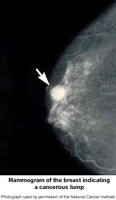

A mammogram is an x-ray examination of the breast. It is used to detect and diagnose breast disease in women who either have breast problems such as a lump, pain, or nipple discharge, as well as for women who have no breast complaints.

Mammography cannot prove that an abnormal area is cancer, but if it raises a significant suspicion of cancer, tissue will be removed for a biopsy. Tissue may be removed by needle or open surgical biopsy and examined under a microscope to determine if it is cancer.

screening mammogramA screening mammogram is an x-ray of the breast used to detect breast changes in women who have no signs of breast cancer. It usually involves two x-rays of each breast. Using a mammogram, it is possible to detect a tumor that cannot be felt.